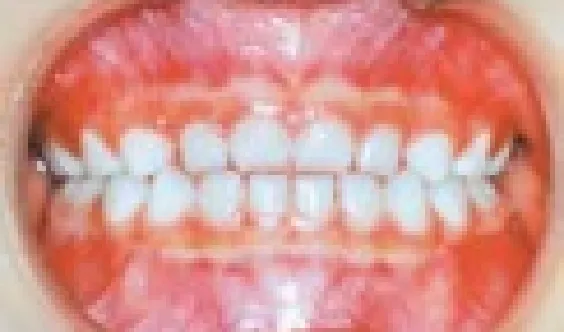

• 虫歯の無いきれいな永久歯列

むし歯の無い

きれいな永久歯